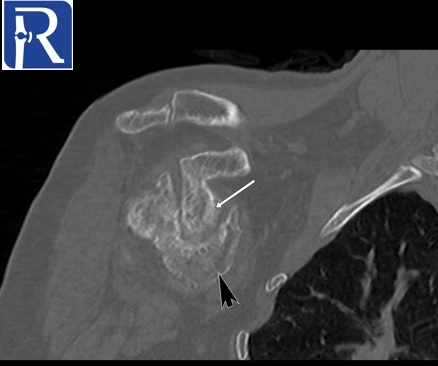

Demographic and clinical details: 70-years-old female patient, admitted with right shoulder pain and restricted motion.

Image Details: AP X Ray shows the inferior glenohumeral joint dislocation with non-united neck fracture (yellow arrow=. Note also deformation of humerus head (black arrow) and glenoid (white arrow). You can notice also superior cortical compression of humerus head consistent with hill sachs lesion. These findings are better seen on CT images.